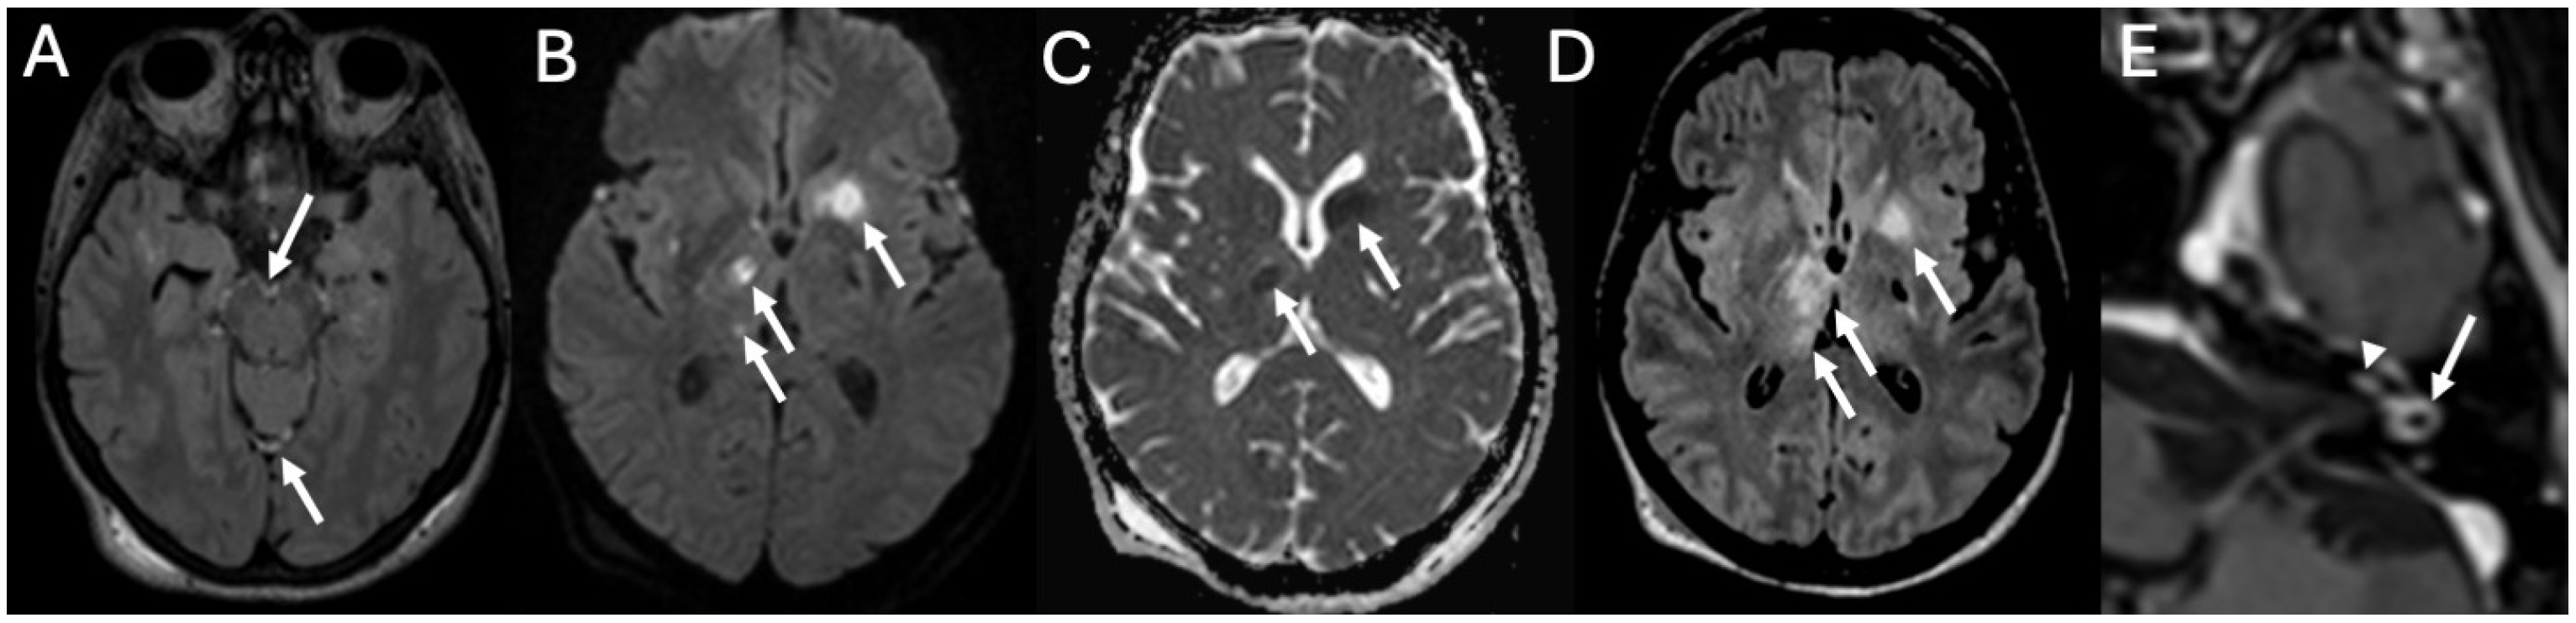

3.1. Otomastoiditis

3.1.1. Imaging

3.3.2. Complications

3.4. Labyrinthitis and Vestibulocochlear Neuritis

Imaging